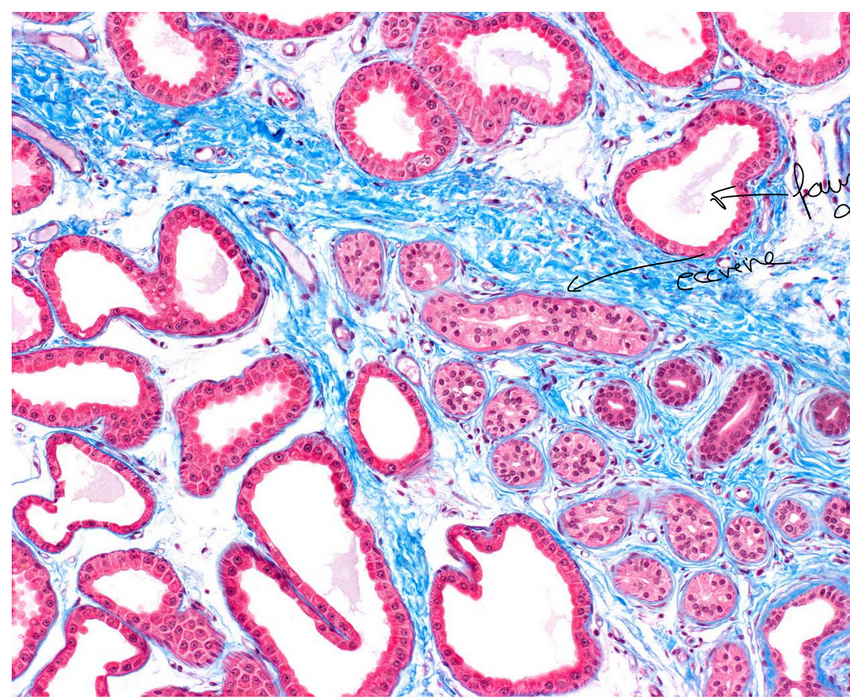

glande sudoripare eccrine

glande sudoripare faussemtn apocrine

exocrine, simple, tubulaire pelotonne, sueur, merocrinie

exocrine, simple, tubulaire pelotonne, sueur, eccrine